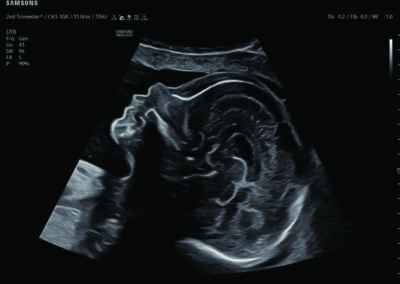

Comprehensive, advanced and expert MFM care for high-risk pregnancies